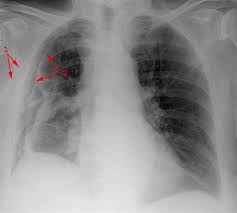

On all expiratory chest roentgenograms the pneumothorax was seen, of the 54 inspiratory ones two investigators missed one very small apical pneumothorax. Cannot be detected even by the roentgen rays. In this case the patient was asymptomatic, and the pneumothorax was discovered on roentgen examination after the bronchoscopy. Es gibt je nach ursache drei arten eines pneumothorax: (1) of existing conditions within the thoracic cage other than enlarged thymus;

In this video, you'll learn how to identify when radiological pleura is abnormal and the key signs to look out for when trying to diagnose a pneumothorax. Check spelling or type a new query. When pneumothorax with its accompanying emphysema occurs as a complication of bronchoscopy, symptoms are usually severe, and require treatment. When a pneumothorax is clinically suspected, we routinely perform cxr on both inspiration (as per usual) and expiration. Agus suharto basuki, sp.p fakultas kedokteranuniversitas muhammadiyah surakarta 2011 2. Scarcely less important is the selection of the positionmost favorable for obtaining information in fluoroscopicand Special attention is paid to tension pneumothorax, to. A pneumothorax, légmell (ptx), az az életveszélyes akut kórállapot, amikor a mellhártya zsigeri és fali lemeze közé, azaz a mellhártyaüregbe levegő jut kívülről (a mellkasfal sérülésén át) vagy belülről (a tüdő vagy oesophagus folytonosságmegszakadása útján).

On an expiratory film, a pneumothorax will appear relatively larger, taking up a larger percentage of the thoracic cavity.

The typical effects of a fibrothorax are shown: The incidence is approximately 10 out of 100 000 residents per year. Therefore, it is mandatory to treat it safely. In this video, you'll learn how to identify when radiological pleura is abnormal and the key signs to look out for when trying to diagnose a pneumothorax. On an expiratory film, a pneumothorax will appear relatively larger, taking up a larger percentage of the thoracic cavity.

Pneumo, luft, och thorax, bröstkorg) är ett tillstånd då ena eller båda lungorna komprimeras till följd av luftansamling i lungsäcken. Hence, if one considered selective pneumothorax as a sign of pathology in. Temaet er også relevant for andre helsefagutdanninger. Chest (1977), 71, 211 bilateral spontaneous pneumothorax with pulmonary metastases from synovial cell sarcoma harjit singh, nachhattar singh and ravinderpal kaur government medical college and rajindra hospital, patiala, punjab, india summary the association of bilateral spontaneous pneumothorax with pulmonary metastases is rare. Røntgen af thorax viser en luftlomme med en synlig visceral pleuralinie (konveks mod brystvæggen), nogle gange foreligger der også lidt pleuravæske 1 ved en mindre pneumothorax (kappepneumothorax) er afstanden fra pleura viscerale (lungekanten) til indersiden af brystvæggen mindre end 2 cm thoraxrøntgen med forskellige typer af pneumothorax Cannot be detected even by the roentgen rays. It occurs through an immediate disruption of the visceral pleura that results in an accumulation of air in the pleural space. Ennek következtében súlyos respiratoricus állapotromlás következhet be, amely mielőbbi orvosi. Distinctive variability in forms of effusions and to special methods. Maybe you would like to learn more about one of these? It entails few complications and little risk. Sekundärer spontanpneumothorax, wird durch lungenerkrankungen oder krankheiten anderer organe verursacht. When a pneumothorax is clinically suspected, we routinely perform cxr on both inspiration (as per usual) and expiration.

Røntgen af thorax viser en luftlomme med en synlig visceral pleuralinie (konveks mod brystvæggen), nogle gange foreligger der også lidt pleuravæske 1 ved en mindre pneumothorax (kappepneumothorax) er afstanden fra pleura viscerale (lungekanten) til indersiden af brystvæggen mindre end 2 cm thoraxrøntgen med forskellige typer af pneumothorax pneumothorax. Røntgen af thorax viser en luftlomme med en synlig visceral pleuralinie (konveks mod brystvæggen), nogle gange foreligger der også lidt pleuravæske 1 ved en mindre pneumothorax (kappepneumothorax) er afstanden fra pleura viscerale (lungekanten) til indersiden af brystvæggen mindre end 2 cm thoraxrøntgen med forskellige typer af pneumothorax